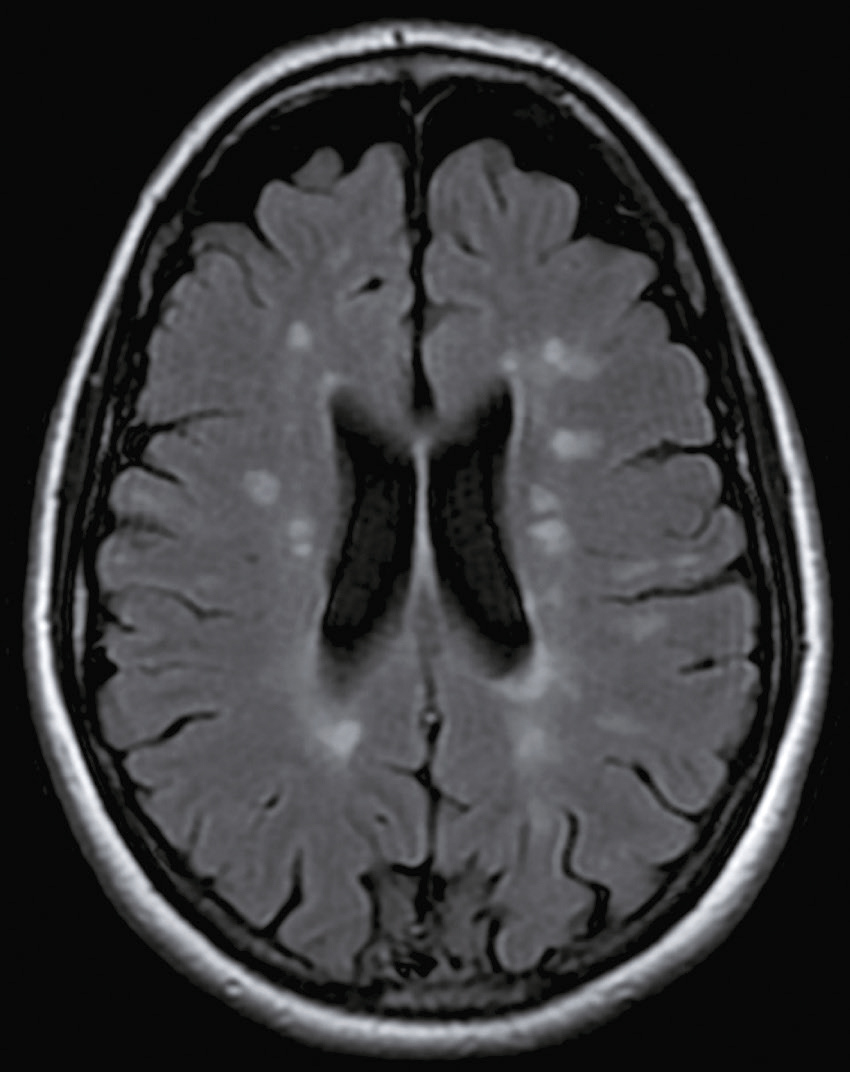

Une nouvelle IRM cérébrale est réalisée devant cette diplopie. Décrivez le cliché (fig. 31.1).

- C hypersignaux de la substance blanche périventricu-laire

- D hypersignaux du tronc cérébral

- E hypersignaux juxtacorticaux